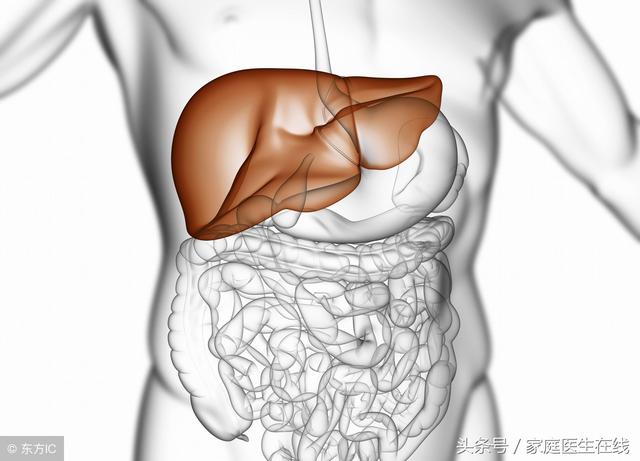

肝臟是我們人體中非常重要的器官,不但可以幫助我們排出體內的廢物,還可以分解我們體內的毒素。如果我們的肝臟出現了問題,不但很容易使我們處於亞健康的狀態,還容易誘發肝癌等一係列致死的疾病。下麵我們就來了解一下,哪些食物可以幫助我們保護肝臟。